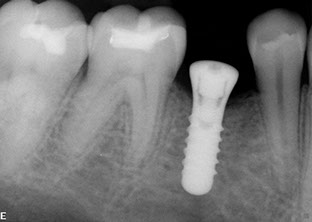

Dental implants

Dental implants have been used for decades to provide a stable support for missing teeth. Implants can be used to stabilize dentures, act as anchors for a bridge, or replace single teeth that are missing.

Implants are designed to be incorporated into the structure of the jawbone. A crown is then attached to the implant to function as a normal tooth. In most cases, implants take several months from placement to the final restoration(s). There is a period of healing while the implant becomes part of the body and stabilizes.